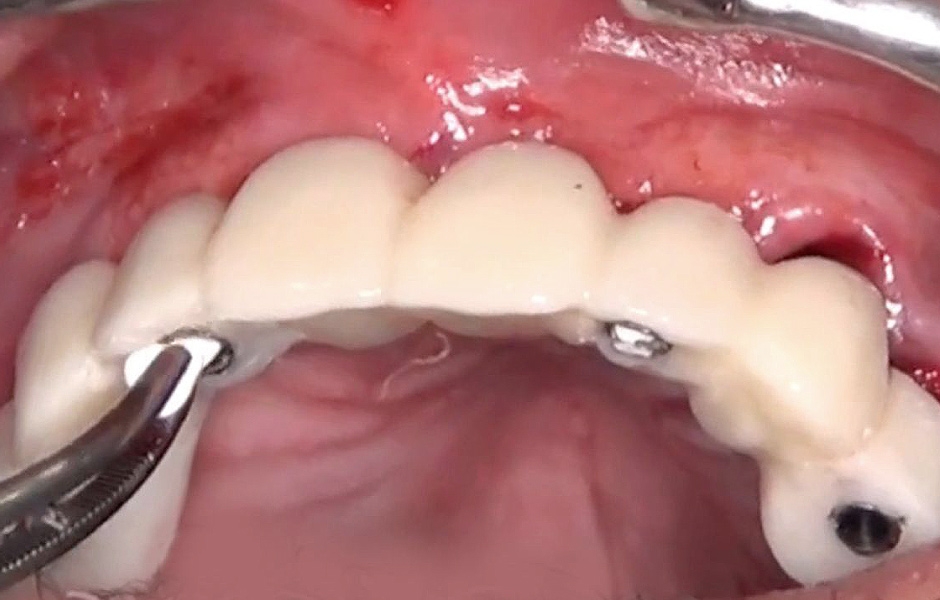

Byl zvolen protokol okamžitého zatížení implantátů s rovnoměrným rozložením sil na celou provizorní náhradu kotvenou dočasnými abutmenty. Prostory mezi abutmenty a provizorní náhradou byly vyplněny (obr. 36–38). Nadbytečný materiál byl odstraněn a provizorní náhrada byla následně vyleštěna, aby byl zajištěn hladký povrch (obr. 39). Pacient obdržel šroubovanou provizorní náhradu v den zavedení implantátů, která byla bezpečně přišroubována k titanovým abutmentům točivým momentem 15 Ncm (obr. 40). Byla zkontrolována okluze (obr. 41, 42). Následně byly pacientovi poskytnuty instrukce pro ústní hygienu.

Obr. 40

Obr. 41